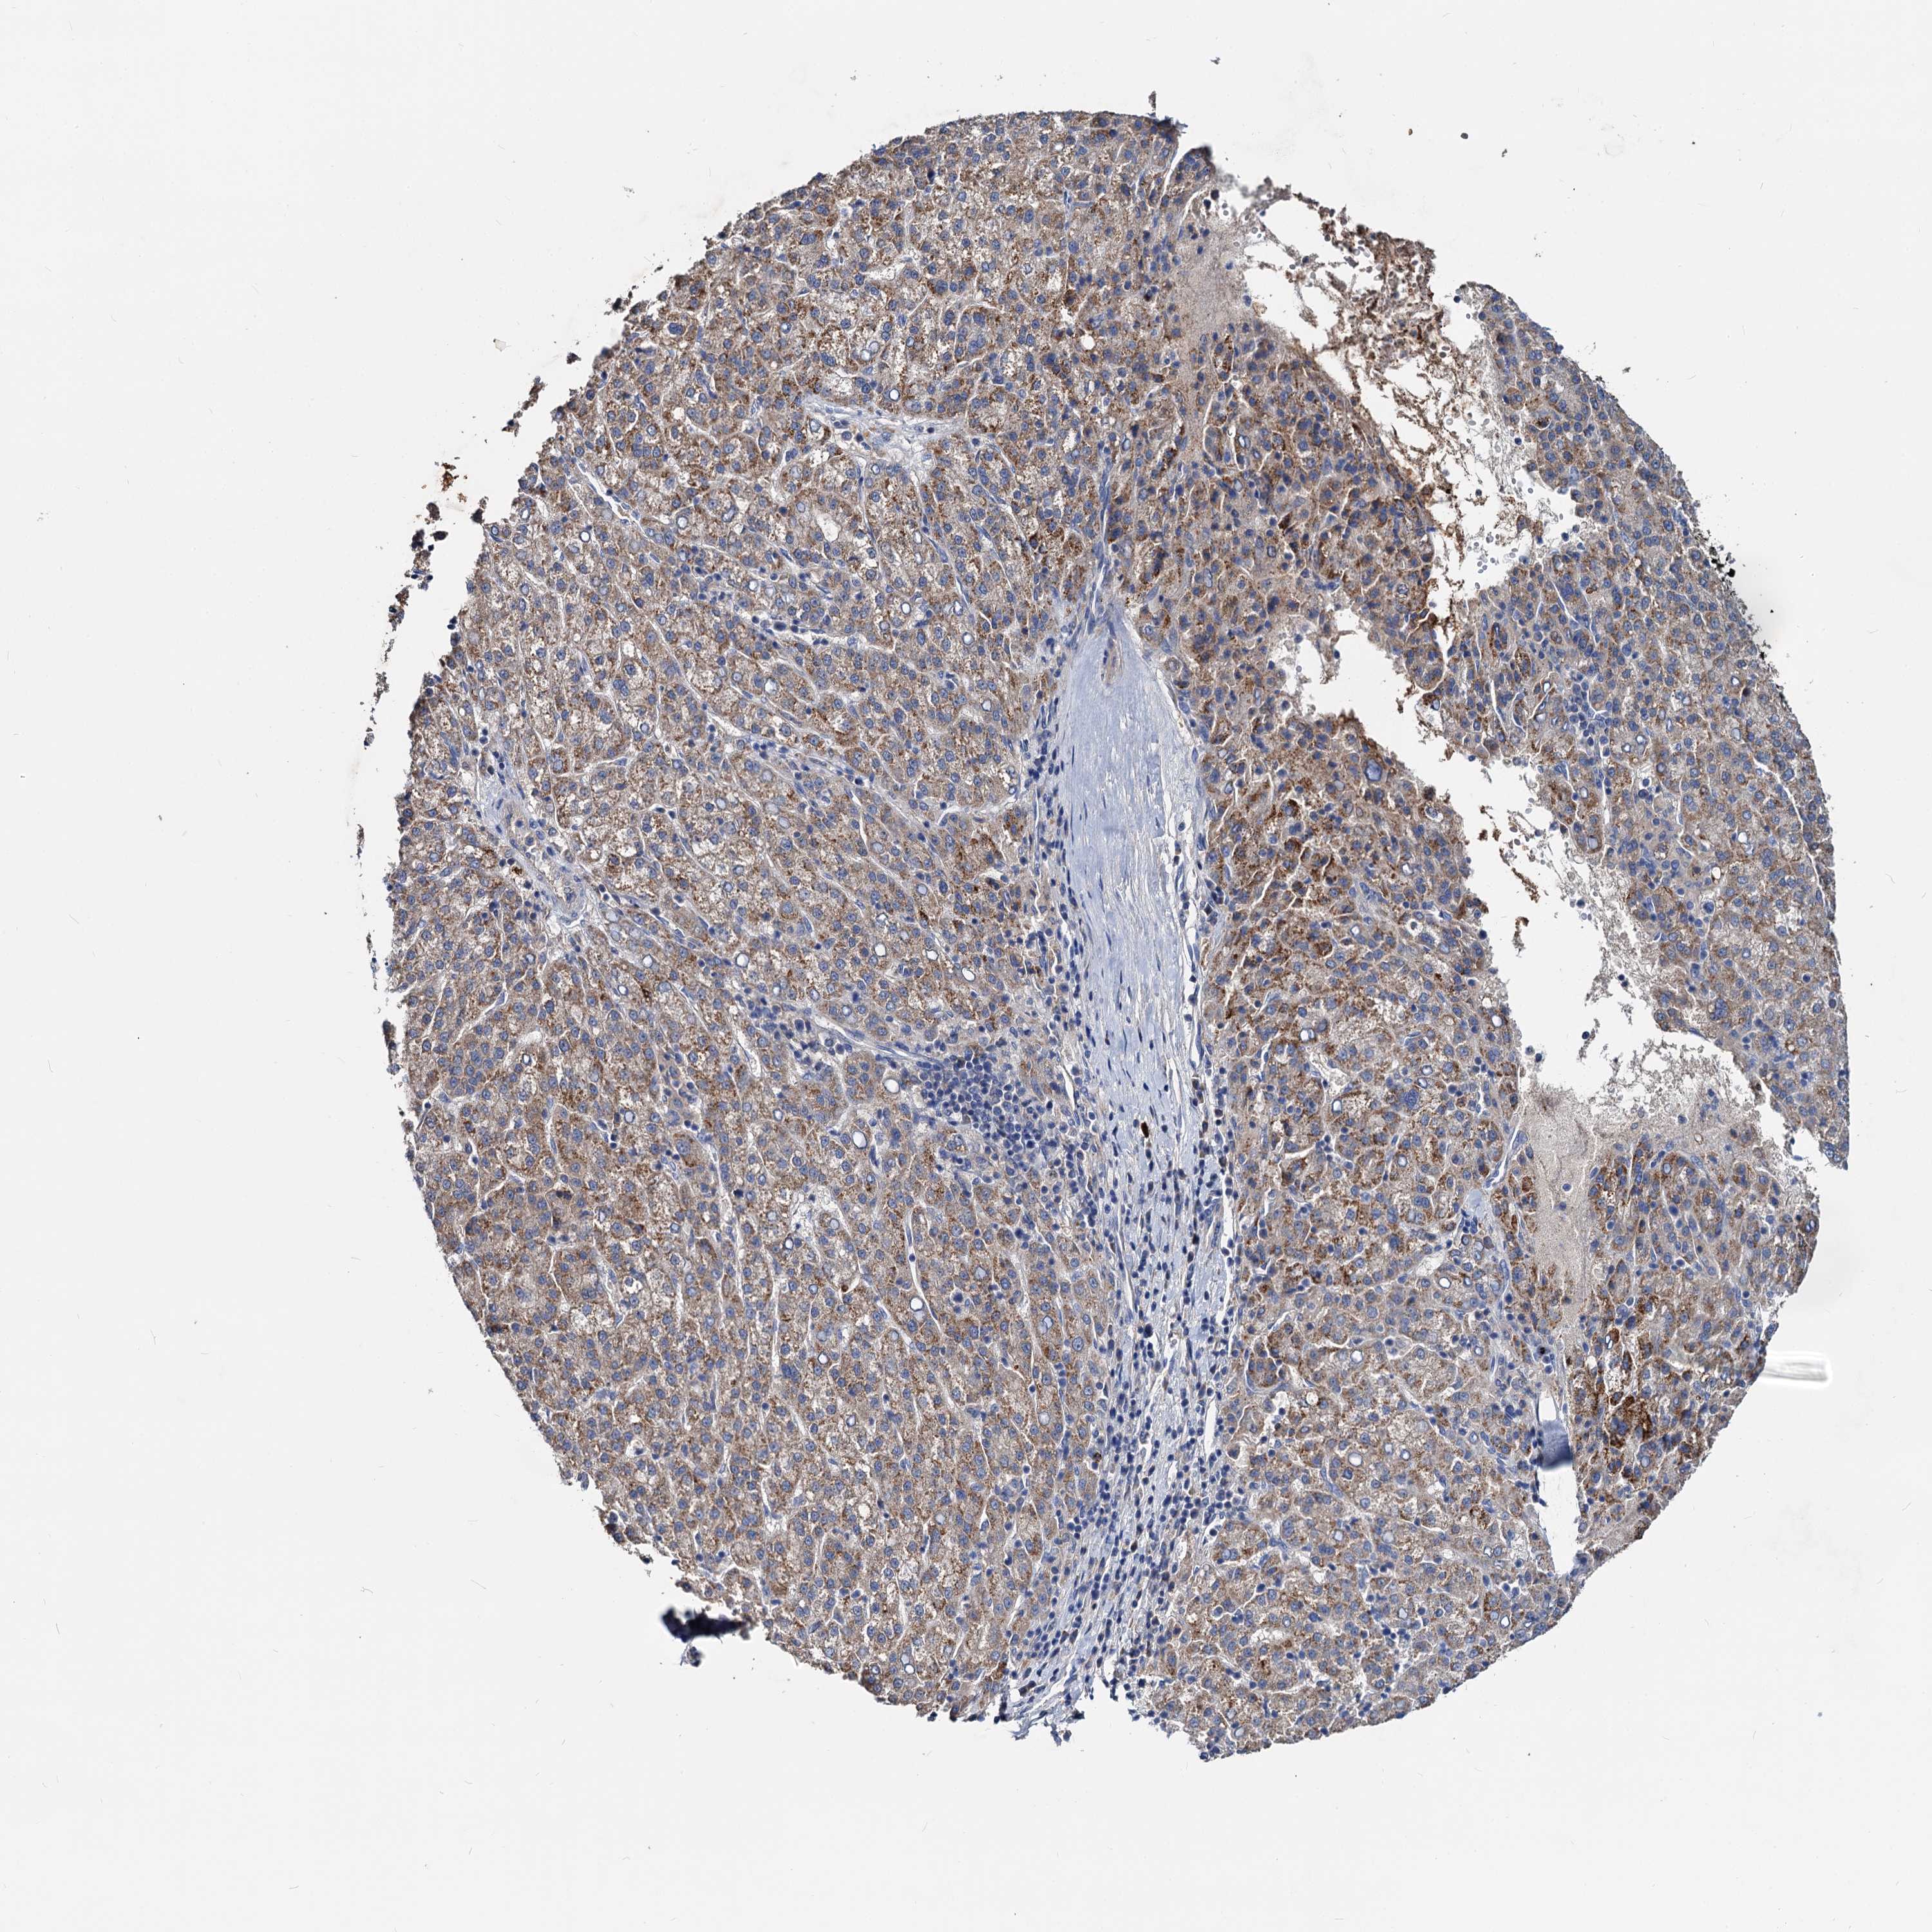

LIVER CANCER - Protein expressioni

A mouse-over function shows sample information and annotation data. Click on an image to view it in a full screen mode. Samples can be filtered based on level of antibody staining by selecting one or several of the following categories: high, medium, low and not detected. The assay and annotation is described here.

Note that samples used for immunohistochemistry by the Human Protein Atlas do not correspond to samples in the TCGA dataset.

Antibody stainingi

Antibody staining in the annotated cell types in the current human tissue is reported as not detected, low, medium, or high, based on conventional immunohistochemistry profiling in selected tissues. This score is based on the combination of the staining intensity and fraction of stained cells.

Each image is clickable and will lead to virtual microscopy that enables deeper exploration of all samples and also displays staining intensity scores, fraction scores and subcellular localization as well as patient and tissue information for each sample.

Antibody HPA039219

Antibody HPA048187

Staining

High

Medium

Low

Not detected

Intensity

Strong

Moderate

Weak

Negative

Quantity

>75%

75%-25%

<25%

None

Location

Nuclear

Cytoplasmic/membranous

Cytoplasmic/membranous,nuclear

Cholangiocarcinoma

Carcinoma, Hepatocellular, NOS